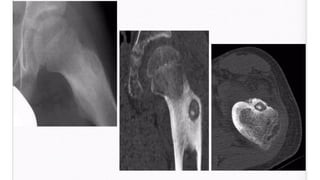

GCT O s t e o c l a s t o m a s

• • Age

• • 20-40 y e a r s

• • 3% develop in immature skeleton

• • L o c a t i o n

• •around the knee: distal femur and proximal tibia: 50-65%

• • distal radius: 10-15%

• • sacrum: 4-10%

• • vertebral body: 5-10%

• A lucent lesion typically situated beneath the articular surface

• E c c e n t r i c

• Narrow z o n e o f transition

• 'soap-bubble' pattern of calcification

• No sclerotic margin

• • overlying cortex is thinned, expanded or deficient

• • Soft-tissue mass may be present

• • No calcification or ossification until complicated by f r a c t u r e

• • CT Scan & MRI

• • To delineate soft tissue extension

• • B o n e s c a n

• • Increased activity in blood-pool phase

Plain film & CT features